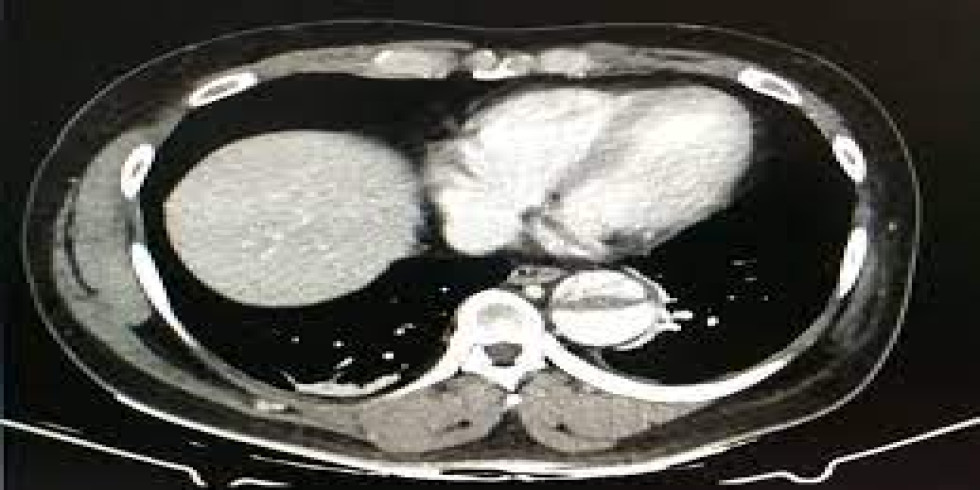

A CT coronary angiogram, also known as CTCA, is a non-invasive imaging test that uses X-rays and a contrast dye to visualize the coronary arteries and detect blockages or other abnormalities. It helps diagnose coronary artery disease by highlighting the arteries and any potential issues within them. Here's a more detailed explanation: What it is: CTCA uses a CT scanner and a contrast dye (usually iodine-based) injected into a vein, typically in the arm, to visualize the coronary arteries. The contrast dye highlights the arteries, making them appear bright on the images produced by the CT scanner, allowing doctors to see the blood flow and identify any blockages or narrowing. How it works: 1. Preparation: Patients may need to avoid eating and drinking for a certain period before the scan and may be given medication to slow their heart rate for clearer images. 2. IV Insertion: An intravenous line (IV) is inserted into a vein, usually in the arm, to administer the contrast dye. 3. Scanning: The patient lies on a table that moves into the CT scanner (a doughnut-shaped machine). The scanner rotates around the patient, taking multiple X-ray images. 4. Image Acquisition: The contrast dye highlights the coronary arteries, allowing doctors to evaluate their structure and identify any blockages, plaque buildup, or other abnormalities. 5. Post-Procedure: Patients can usually resume normal activities immediately after the scan, but may be advised to drink plenty of fluids to help flush out the contrast dye. Purpose: Detect Blockages: CTCA is used to identify blockages or narrowing (stenosis) of the coronary arteries, which can be a sign of coronary artery disease. Assess Plaque Buildup: It can detect the presence and extent of plaque buildup (atherosclerosis) in the arteries, which can restrict blood flow. Evaluate Heart Disease Risk: CTCA helps assess the overall risk of heart disease and can guide treatment decisions. Guide Further Procedures: If significant blockages are found, CTCA can help determine if further procedures like angioplasty or bypass surgery are needed. Potential Risks: Allergic Reaction: A small percentage of patients may experience an allergic reaction to the contrast dye, ranging from mild (itching, hives) to severe (difficulty breathing, anaphylaxis). Kidney Problems: In rare cases, contrast dye can potentially harm the kidneys, especially in patients with pre-existing kidney conditions. Radiation Exposure: CTCA involves exposure to X-ray radiation, but the dose is generally considered low and safe for most patients.